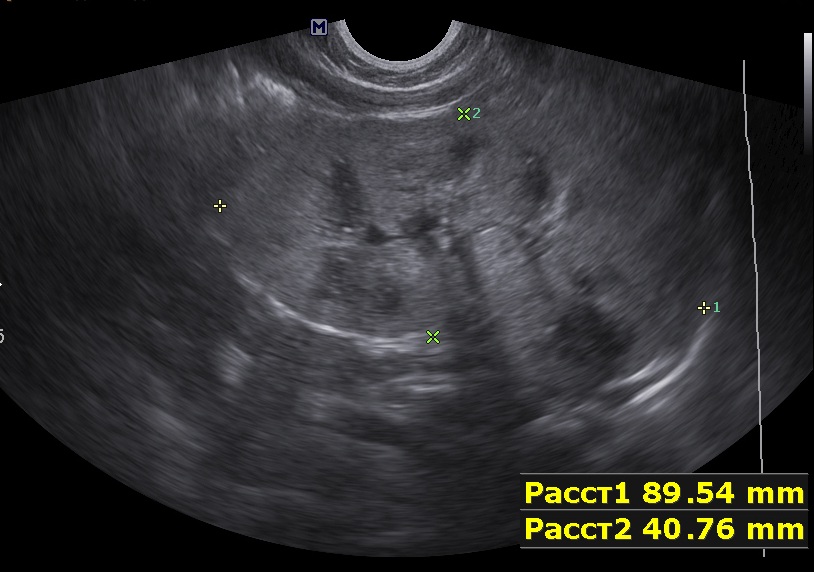

Ребенок 9мес, старшая сестра 9лет с ювенильным поликистозом (в н.в. ХБП 2).

Первые изменения в 1 мес, увеличение размеров почек.

Осмотрен мной ребенок впервые, обращено внимание на большие почки, 90х40мм, паренхима 17-18мм, корковый слой гиперэхогенный, пирамидки дифференцируются. Линейным датчиком определяется: кисты или расширенные канальцы в пирамидках. Структура печени в 1 мес была не изменена, в н.в. отмечается перипортальный фиброз, размеры печени и селезенки увеличены.

Поставил медуллярную кистозную дисплазию, почитав литературу предполагаю нефронофтиз Фанкони, но к сожалению не нашел картинки только описание данной болезни. Поделитесь своим мнением.

правая почка.jpg